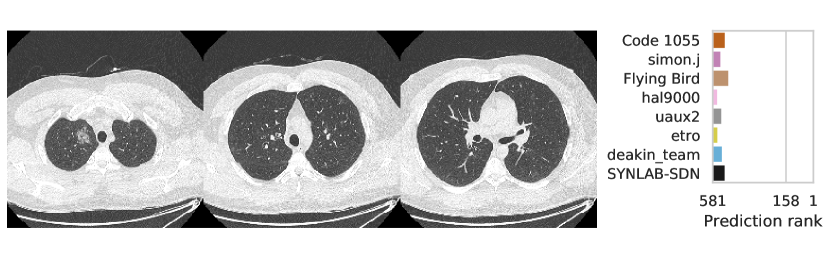

3.2.3 Performance

Table 1 shows the AUC on test set B for COVID-19 presence and severity of the teams that submitted to the Final phase. Figure 4 shows Receiving Operating Characteristics (ROC) curves of the six successful Final phase submissions for discriminating between severe and non-severe COVID-19 subjects from test set B. Figures 5 and 6 show how the finalists ranked the subjects from test set B with severe and non-severe COVID-19 respectively for presence of severe COVID-19. Figures 7 and 8 highlight some individual cases from test set B. During the original STOIC project [67], a logistic regression model was developed to predict severe COVID-19 using clinical variables and CT annotations by radiologists. It was developed and evaluated using the patients from the STOIC who were COVID-19 positive for both RT-PCR and CT, and had unenhanced CT. Of these 4238 patients, 1000 developed severe COVID-19. Revel and colleagues 6 reported an AUC for this model of 0.69 (CI: 0.67-0.71). To compare this model against the results from STOIC2021, an ensemble of the top three solutions for severe COVID-19 prediction was evaluated on the 367 patients from test set B who were COVID-19 positive for both RT-PCR and CT, and had unenhanced CT. 97 of these patients developed severe COVID-19. The top three ensemble achieved an AUC of 0.783 (CI: 0.706-0.848).